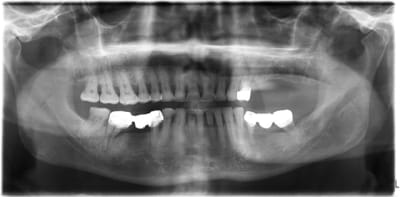

voici mon premier cas d'Extraction implantation Immediate...

on ne voit pas trop sur les photos, mais j’espère que tu avais bien assaini en paro auparavant.. parce que la pano n'est pas très belle...

oui, la pano date du jour de la consult,

on a fait un assainissement paro et d' autres soins on été entrepris entre temps.

Je dis joli cas, sinon comme les autres, un peu timide sur la longueur, t aurais pu largement lui ramoner le bas fond sinusien pour aller poser un 12 mm sur le distal qui est une 6 mm je présume. Je sais, c est un peu facile après coup. ou sinon radio per op mais difficile à gérer sur le plan de l asepsie.

Non canin c'est un 8mm et 10mm en 24 ET 25